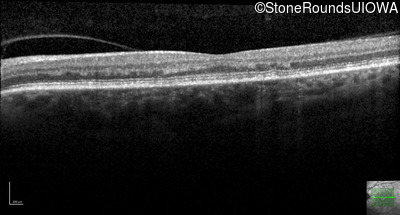

AR Stargardt Disease (IIA)

Age at visit: 59 years (Visit 3)

Diagnosis & molecular findings

Disease Gene Allele 1 variant(s) Allele 2 variant(s) Inheritance mode

AR Stargardt Disease ABCA4 Arg219Thr AGA>ACA Gly863Ala (G)GA>(G)CA AR